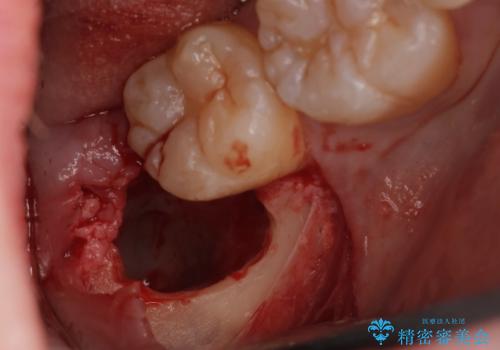

親知らず抜歯

- 20代女性

- 親知らずを抜きたいとのことで来院。CTで神経の位置などを確認し、抜歯を行いました。1週間後には抜糸に来院予定です。

しっかり麻酔が効いていることを確認し抜歯を行いました。

親知らずがあると清掃性が悪くなるため手前の歯の虫歯のリスクが上がるので抜歯をおすすめします。